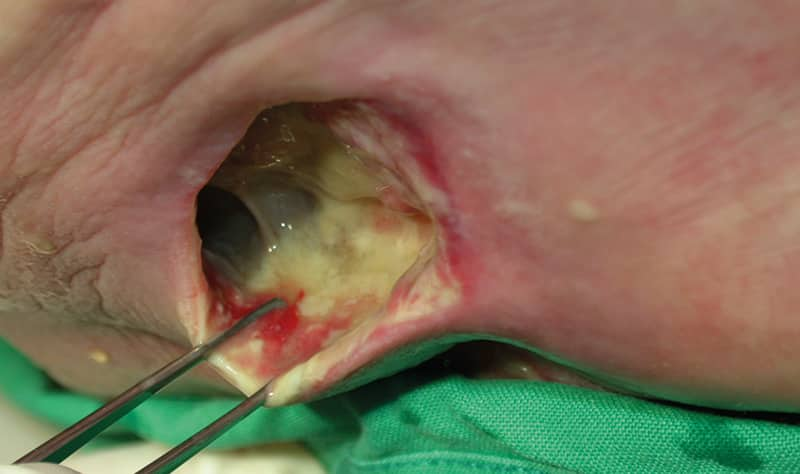

• the wound’s depth, undermining, tunnelling and fistulas

• the underlying wound bed structure and topography

• the tissue quality. Are there signs of granulation or necrosis?

• the periwound (surrounding) skin and the wound edge